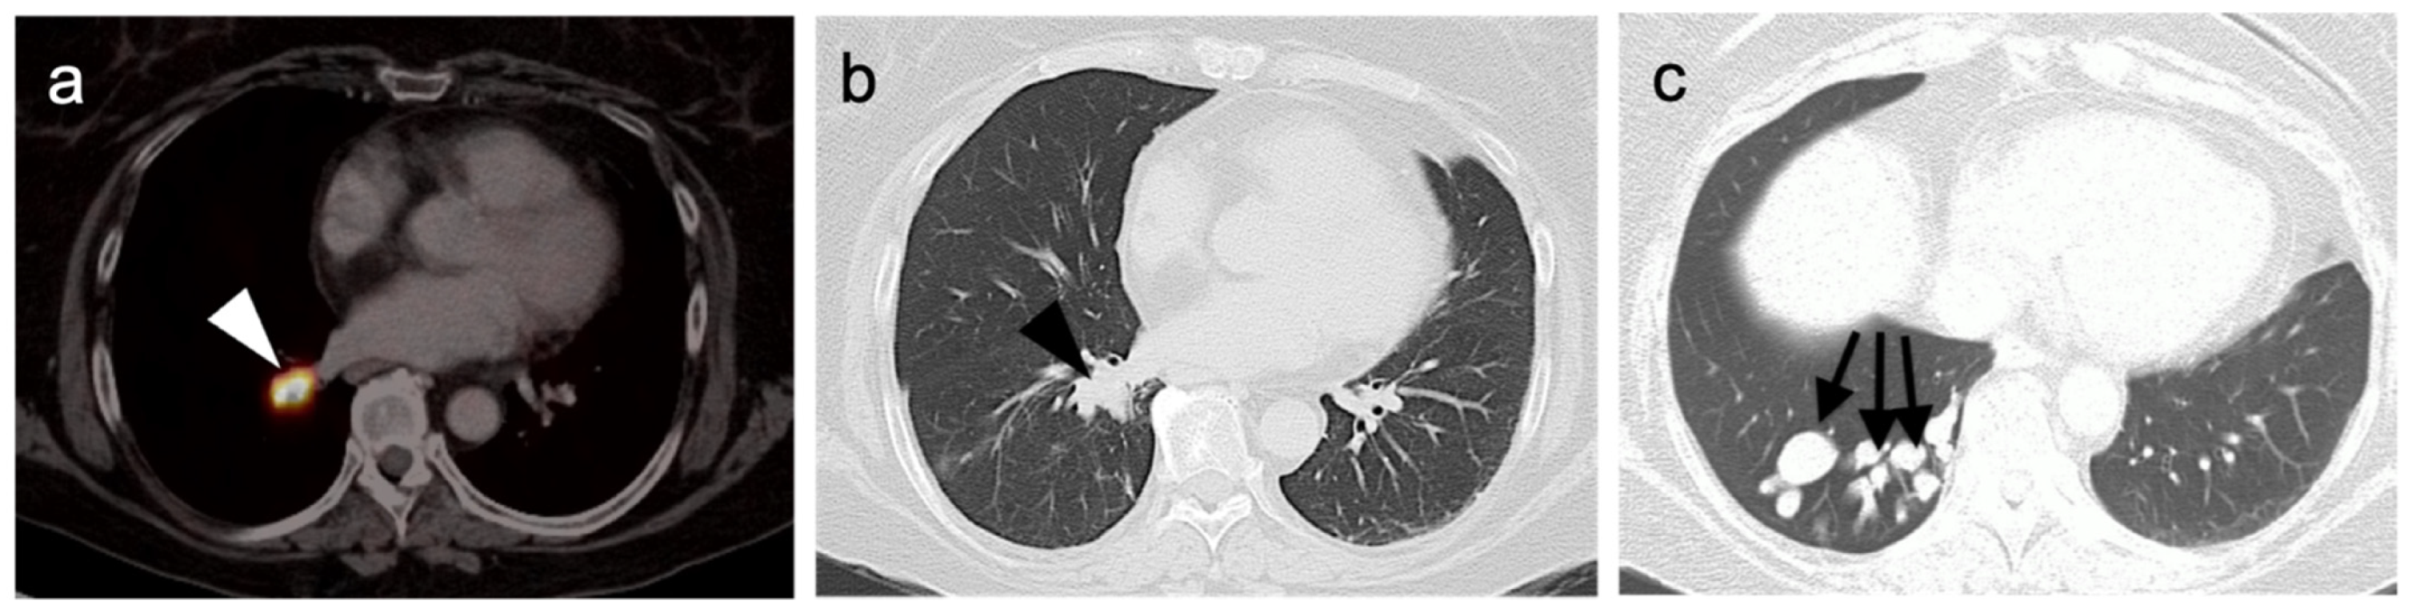

4.4. Bronchial Carcinoid